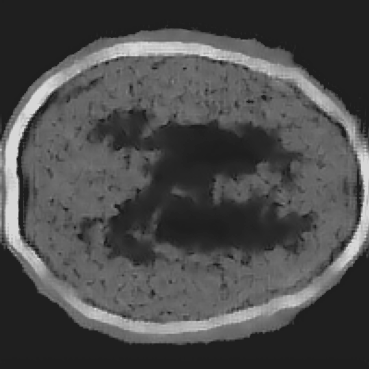

Figure 8: Comparison between physics-based FWI and the proposed BrainPuzzle reconstruction. (a) Homogeneous initial SoS; (b) FWI result using homogeneous initial model; (c) Smoothed initial SoS; (d) FWI result using smoothed initial model; (e) BrainPuzzle SoS reconstruction; (f) Ground truth. BrainPuzzle yields accurate and detailed structures even without a high-quality initial model.

Additionally, we also compare BrainPuzzle with the physics-based FWI with results illustrated in Figure 8. The physics-based FWI is conducted using the steepest descent method over 30 epochs with the full-transducer dataset. We use two different initial models: one with a homogeneous velocity assigned to all tissues inside the skull (Figure 8(a)), and the other obtained by smoothing the ground-truth tissue distribution within the skull (Figure 8(b)). The model with a homogeneous initial condition produces poor results, while the one with a smoothed initial model yields much better outcomes, indicating that the physics-based method relies heavily on the accuracy of the initial guess of SoS. In contrast, Brain Puzzle SoS achieves good results even with the partial-transducer setup as shown in Figure 8(e).